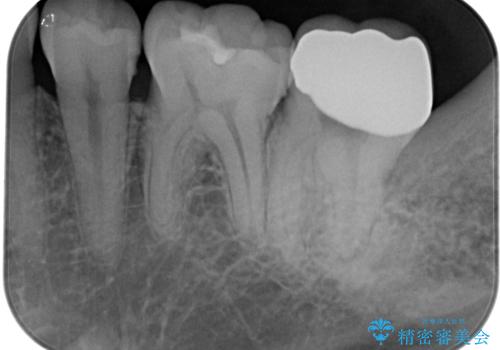

左上の奥歯は神経が失活しており、根管治療が必要な状態でした。

その他は銀歯のインレー(部分的な詰め物)が装着されており、それらはむし歯を除去した後にセラミックインレーにて修復治療を行い、左下と根管治療を行う左上の奥歯はオールセラミッククラウンにて補綴治療を行うこととしました。

根管治療の途中で、矯正治療の後戻りが気になるとのことで、下顎前歯の叢生を改善するためにマウスピース矯正を並行して行いました。